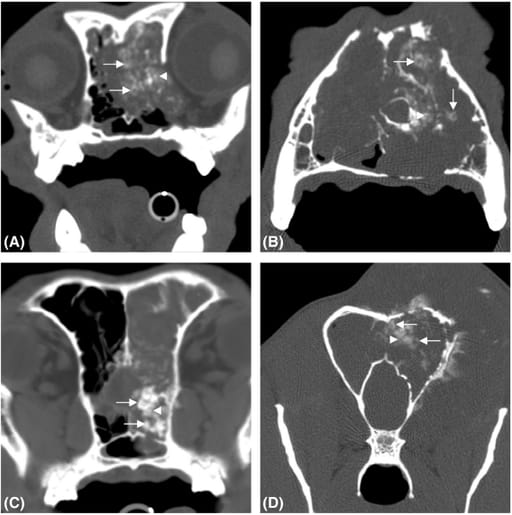

Transverse images of the caudal nasal cavity (A), rostral nasal cavity (B) and frontal sinus (C, D) in bone windows illustrating “popcorn”

calcification with amorphous areas of calcification (arrow heads) and well-defined ring-and-arc shapes (arrows)

Calcification patterns were identified in 8 of 11 cases (73%), with predominant types being popcorn (55%) and ring-and-arc (18%). Popcorn calcification involved amorphous areas overlaid with well-defined arcs, while ring-and-arc calcification presented as small, ring-like areas. Tumors were destructive, expansile masses with mild heterogeneous contrast enhancement. All tumors with calcification were advanced (stage 3 or 4). Lymphadenopathy was rare, with only one case showing mild ipsilateral retropharyngeal node involvement. No cytological evidence of metastasis was observed in the lymph nodes.

CT imaging revealed characteristic calcification patterns, including popcorn and ring-and-arc types, that can aid in differentiating nasal chondrosarcoma from other canine nasal neoplasms. These findings align with patterns described in human chondrosarcoma, suggesting potential diagnostic utility. Histopathology remains essential for definitive diagnosis.